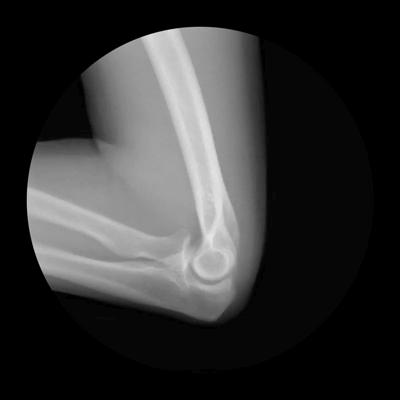

Οι παρακάτω φωτογραφίες, για την ακρίβεια πρόκειται για ακτινογραφίες του ορθοπεδικού Noah Weiss ο οποίος σε συνεργασία με τον φωτογράφο Cameron Drake, δημιούργησαν αυτές τις εκπληκτικές απεικονίσεις. Με τον τρόπο τους, ρίχνουν φως στο τι συμβαίνει στις αρθρώσεις.